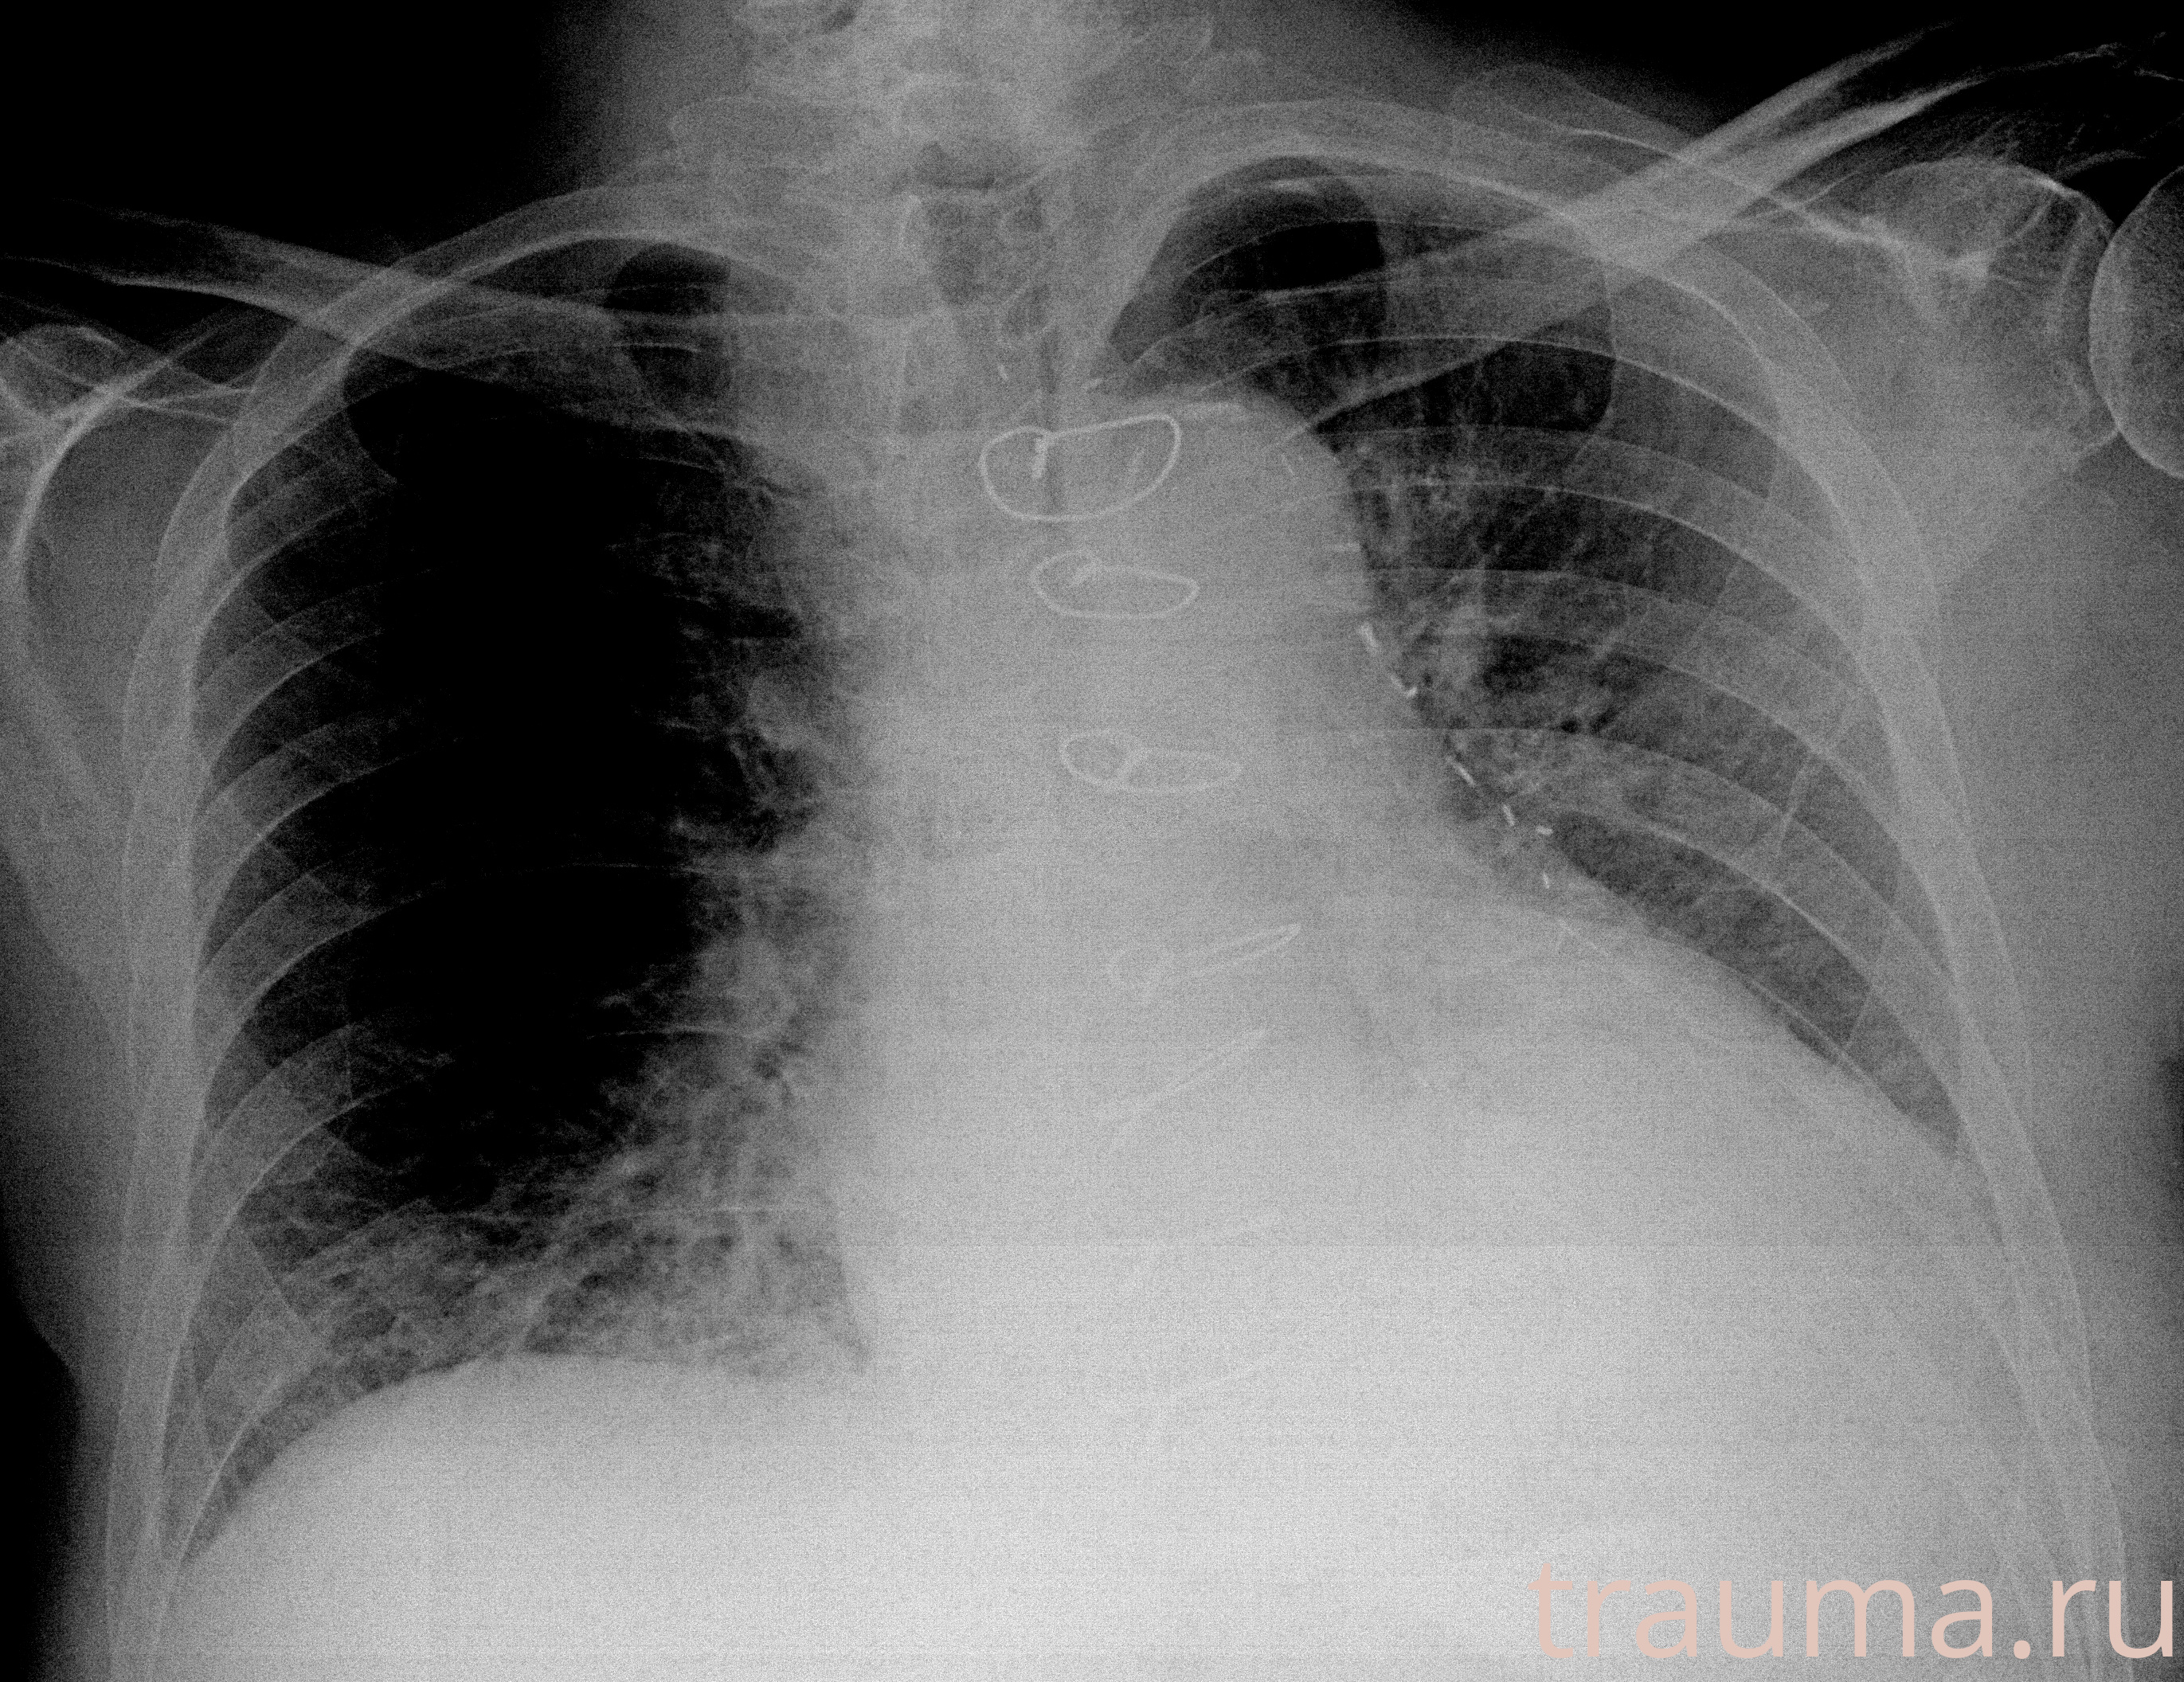

Рентгенограммы

Рентген на дому: по вашему адресу приезжает врач-рентгенолог, травматолог-ортопед с мобильным рентгеновским аппаратом, проводит диагностику травмы или заболевания, делает необходимые рентгенограммы, дает рекомендации по дальнейшему лечению. Получить качественные снимки в домашних условиях возможно благодаря уникальной методике, разработанной МосРентген Центром для института  Склифосовского

Яркость: 1   Контраст: 1   Инвертировать: 0 Увеличение: 1

Перетаскивайте мышь вверх/вниз для контраста, влево/право для яркости. Прокрутка колесом изменяет масштаб. Нажмите Сбросить для возврата к исходному изображению. При увеличении держите мышь в той области, которую хотите рассмотреть.